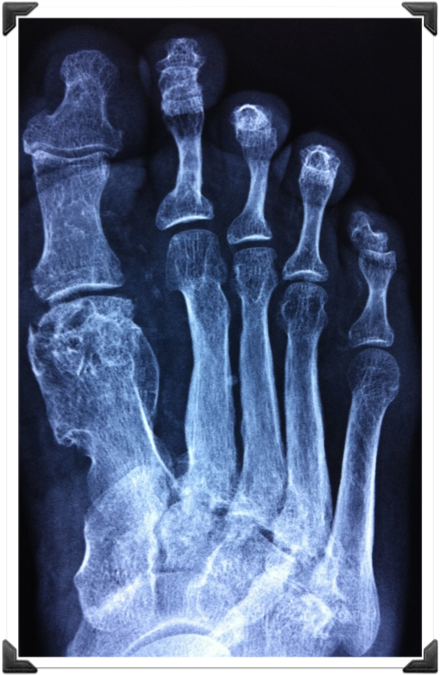

Rx Pre Operatorias

Cabeza del 2do MTT deformidad en flexion

Fusion Interfalangica de 2,3,4 y 5to Dedos

Dr. Luis Villanueva